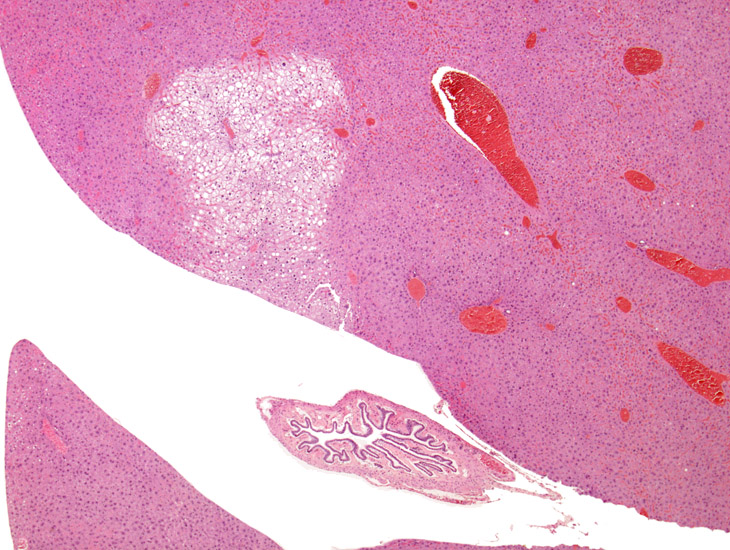

Fatty change, mild. The circular clear spaces represent areas previously occupied by fat in this mouse on a choline deficient diet. The fat is dissolved out by xylene during processing of the tissue.